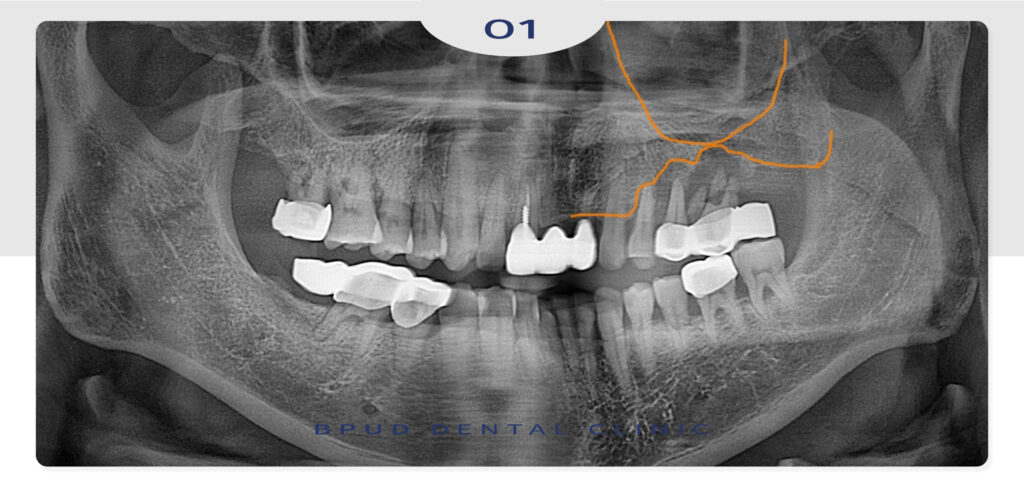

왼쪽 위 작은 어금니부터 큰 어금니까지

모두 충치도 심하게 진행되었고 치주염도

심한 상태라 모두 발치를 하고 임플란트 식립이

필요한 상황임을 설명드렸습니다.

하지만 잇몸뼈가 이미 많이 녹아

많은 양의 뼈이식이 필요하여 상악동 거상술이

함께 필요한 상황이어서 동시에 계획을 수립하여

당일 모두 발치 즉시 상악동 거상술 및 임플란트

식립을 진행하였습니다.